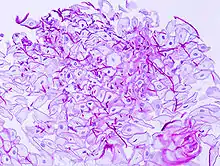

Esophageal candidiasis stained by periodic acid-Schiff procedure